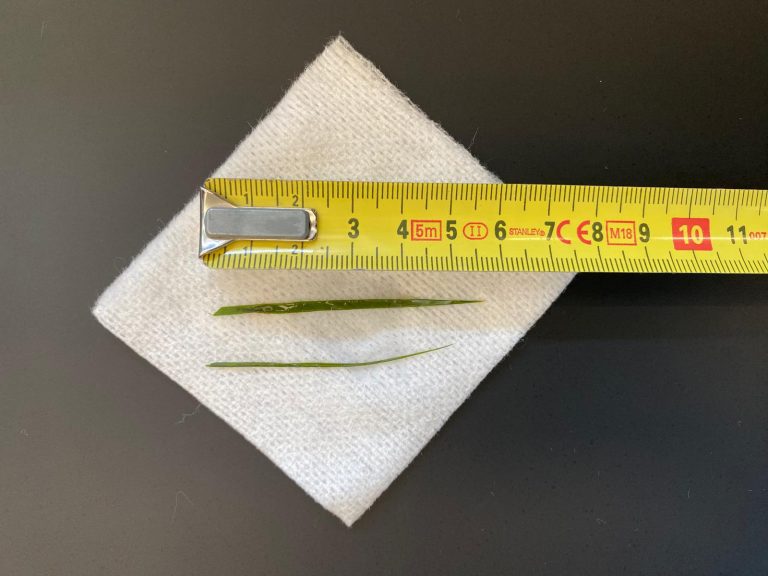

Het werd nog beter toen we de uitslag van het pathologisch onderzoek kregen; Het bleek te gaan om een ontsteking in de darmwand met verval en pusvorming met daarbij een buikvliesontsteking. Het was veroorzaakt door een perforatie van de blinde darm. Met als belangrijkste toevoeging: geen aanwijzingen voor een vorm van kanker. Er was dus eigenlijk sprake van een perforerende blindedarmontsteking. Het was dus niet vreemd dat ze zo’n buikpijn had.